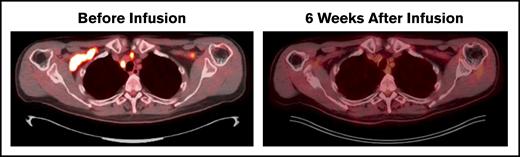

Disease evaluation by PET/CT before receiving lymphodepletion and CD30 CAR T cells showed involvement of bilateral cervical, supraclavicular, and mediastinal nodes as well as a single mesenteric node. All locations completely resolved 6 weeks after CD30 CAR T-cell therapy (Figure 2). Routine imaging at 24 months revealed continued remission, and the patient remains clinically well on follow-up physical examinations more than 30 months after treatment.

Durable CR after CD30 CAR T-cell therapy. Patient with multiply relapsed EATL. Before lymphodepletion and CD30 CAR T-cell infusion, disease involved the bilateral cervical, supraclavicular, mediastinal, hilar, and a single mesenteric lymph node. Six weeks after infusion, the patient achieved a Deauville score of 1 and CR. Additional disease assessments at 6, 12, and 24 months have continued to show CR.

Durable CR after CD30 CAR T-cell therapy. Patient with multiply relapsed EATL. Before lymphodepletion and CD30 CAR T-cell infusion, disease involved the bilateral cervical, supraclavicular, mediastinal, hilar, and a single mesenteric lymph node. Six weeks after infusion, the patient achieved a Deauville score of 1 and CR. Additional disease assessments at 6, 12, and 24 months have continued to show CR.